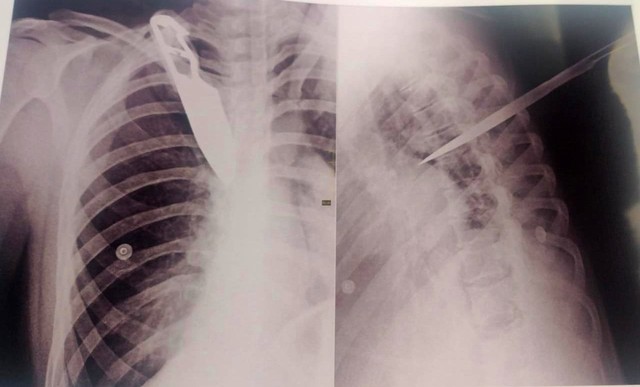

Uma imagem de um exame de raio-X mostra a faca cravada nas costas da mulher atingida pelo ex-companheiro, que é detento e estava em 'saidinha' de fim de ano, durante uma discussão, na terça-feira, 28, em Garça (SP) (110 km de Ourinhos). As informações são do g1.